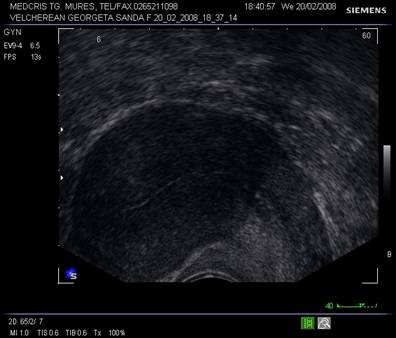

Ecografia abdominala si transvaginala trebuie sa raspunda suspiciunilor legate de malignitate sau benignitate. In functie de tipul de ecogenitate interna, tumorile ovariene se pot clasifica in [2,5,6] :

tumori ovariene pur chistice

Tumori ovariene chistice

compartimente (uniloculare - multiloculare)

grosimea peretilor si a septurilor

ecogenitatea interioara generala

prezenta de ecogenitati interne organizate, distributia acestora, etc